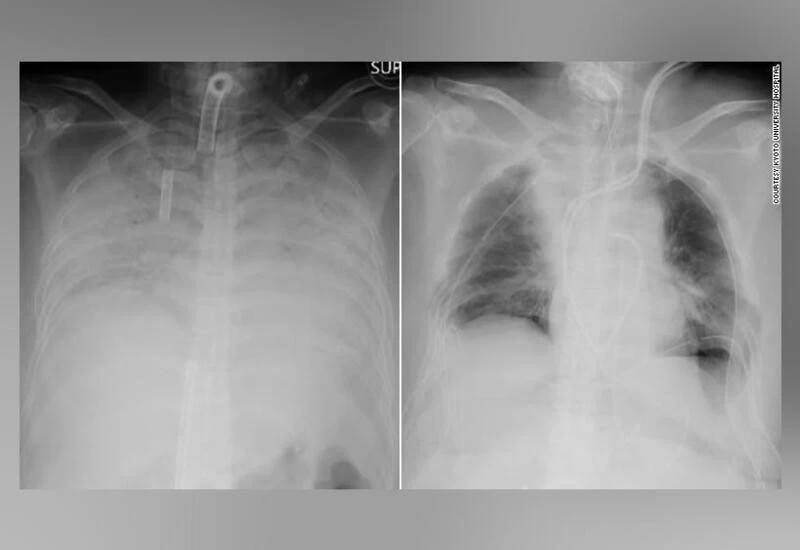

टोक्यो: जापानी चिकित्सकों को कोरोना से पीड़ित एक महिला के बुरी तरह खराब हो चुके फेफड़े के प्रत्यारोपण में बड़ी कामयाबी मिली है। मृतक डोनर के फेफड़े को प्रत्यारोपित करने के कई सफल ऑपरेशन विश्व भर में हो चुके हैं मगर यह पहली बार है जब किसी जीवित डोनर ने अपने फेफड़े का कुछ हिस्सा दान किया है।

क्योटो यूनिवर्सिटी हॉस्पिटल ने कहा, 30 डॉक्टरों की टीम ने 11 घंटे की कोशिश के बाद इसमें कामयाबी पाई। महिला के फेफेड़े में उसके पति और बच्चे के फेफड़े का कुछ हिस्सा ट्रांसप्लांट किया गया है।

गौरतलब है, कोरोना संक्रमण के कारण फेफड़े के खराब होने के कई मामले अमेरिका में भी सामने आ चुके हैं। लेकिन इनमें मरीजों को बचाने के लिए डॉक्टरों ने मृत डोनर के अंगों का इस्तेमाल किया था। हॉस्पिटल के अनुसार यह पहली बार है जब एक जीवित डोनर के फेफड़े का कुछ हिस्सा कोरोना मरीज को ठीक करने में उपयोग हुआ है।

क्योटो हॉस्पिटल के मुताबिक महिला मरीज जापान के कंसाई की रहने वाली है और उसे पिछले साल कोरोना संक्रमण हुआ था। वह कई महीने से जीवन रक्षक प्रणाली पर थी। महिला के पति और बेटे की हालत स्थिर बताई गई है।